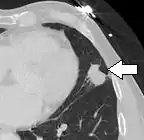

Thin slice and maximal intensity projection of a lung nodule, the latter better visualizing vascular convergence.[9]

• Vascular convergence is where vessels converge to a nodule without adjoining or contacting the edge of the nodule, and is mainly seen in peripheral subsolid lung cancers.[9] It reflects angiogenesis.[9]